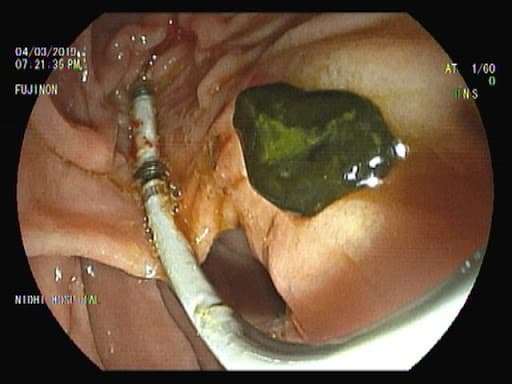

Endoscopic retrograde cholangiopancreatography (ERCP) is a specialized technique used to study and treat problems of the liver, pancreas, and, on occasion, the gallbladder. ERCP is performed under sedation.

To reach the small passageways, known as ducts, that connect these organs, an endoscope is passed through the mouth, beyond the stomach and into the small intestine (duodenum). A thin tube is then inserted through the endoscope into the common bile duct and pancreatic duct connecting the liver and pancreas to the intestine. A contrast material (dye) is injected through the tube and flows into the liver and pancreas, outlining those ducts as X-rays are taken. The X-rays can show narrowing or blockages in the ducts that may be due to a cancer, gallstones, or other abnormalities. During the test, a small brush or biopsy forceps can be put through the endoscope to remove cells for study under a microscope.

ERCP in Ahmedabad can be used to diagnose biliary colic, jaundice, elevated liver enzymes, cholangitis (inflammation of a bile duct), pancreatitis (inflammation of the pancreas), and bile-duct (biliary) obstruction due to gallstones (choledocholithiasis) and cancer. ERCP can be used to treat gallstones, malignant and benign biliary strictures, cholangitis, pancreatic cancer and pancreatitis.